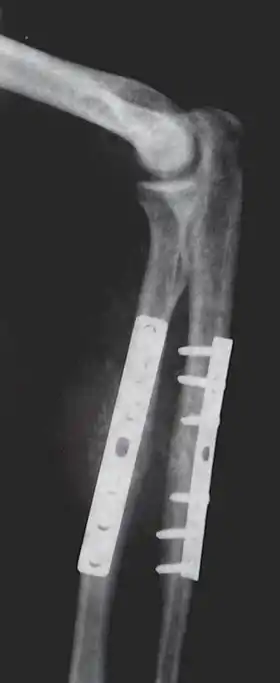

Orthopedic implants to repair fractures to the radius and ulna. Note the visible break in the ulna. (right forearm)